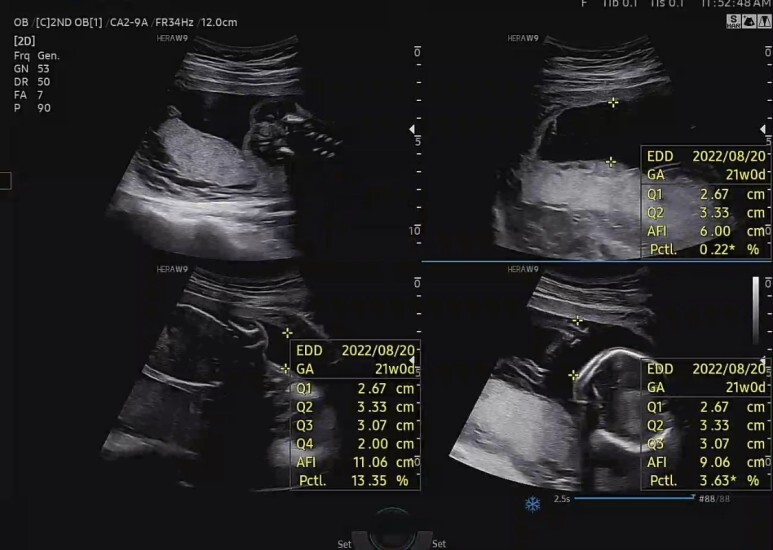

양수량 측정

양수 충분해서 아기 잘 놀 수 있다고 하셨다. 예에~